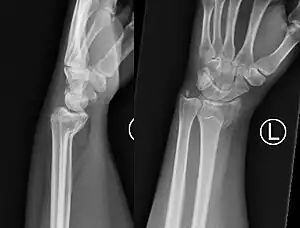

| Colles' fracture | Abraham Colles | distal radius fracture with dorsal angulation, impaction and radial drift | fall on outstretched hand | Colles' fracture at Who Named It? |

|